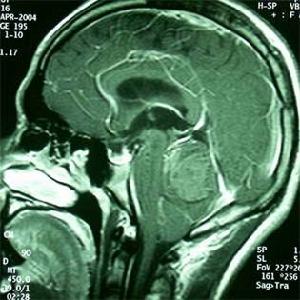

5、顱腦畸形。如顱底凹陷、狹顱症、導水管發育畸形、先天性小腦扁桃體下疝畸形等。